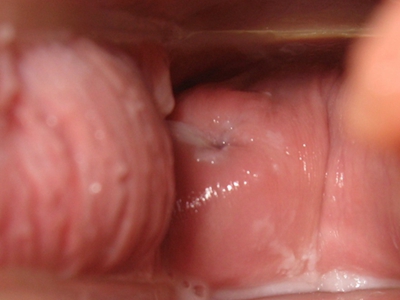

霉菌性外阴炎阴道红肿白带增多图

霉菌性外阴炎累及阴道时,表现为白带增多,阴道黏膜表面附有白色块状物,大小不等,擦除后可露出红肿黏膜面,患者自觉瘙痒、疼痛。